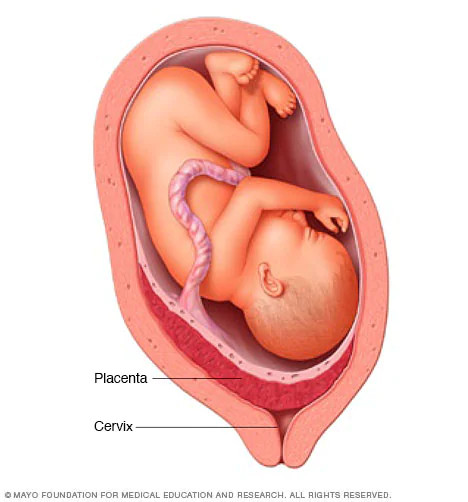

Plasenta Previa

Plasenta previa adalah suatu kondisi kehamilan dimana plasenta menutupi leher rahim secara komplit atau sebagian